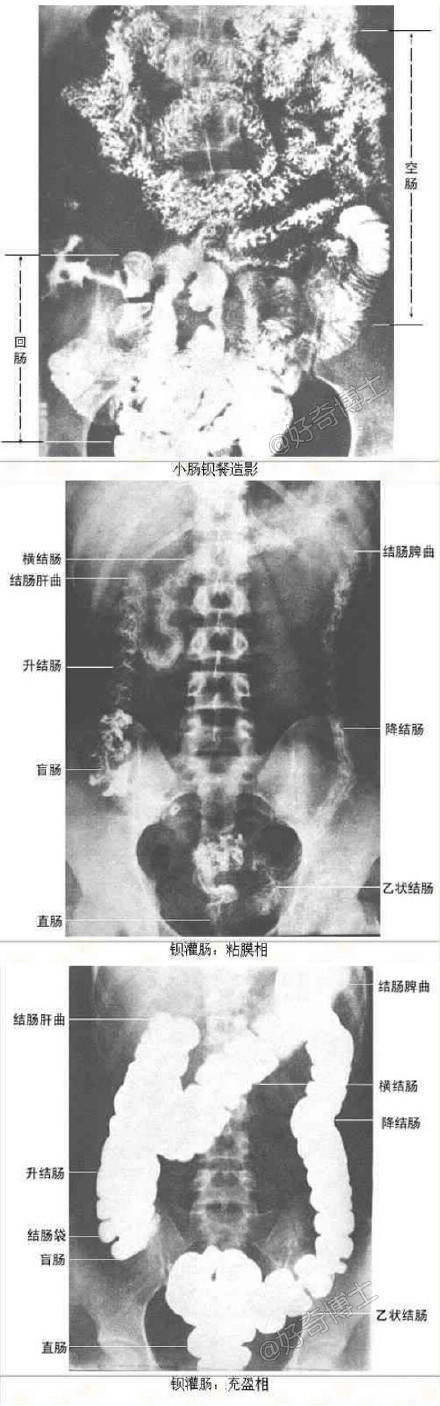

教你如何看X线片子的最全整理

如何看X线片子的最全整理。超珍贵!留起来以后可能用得到!!!